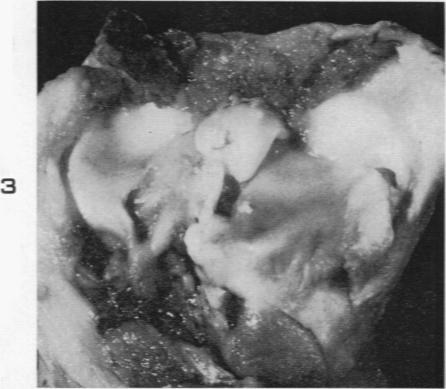

Experimental production of pigmented villonodular synovitis in dogs.

Am J Pathol. 1954 Jul-Aug;30(4):799-811.